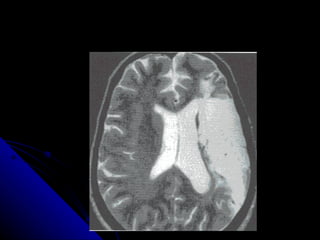

AFASIA DE CONDUCCION El lenguaje espontáneo muestra una articulación fluida, pero con presencia de trastornos anómicos y parafasias fonemicas La comprensión esta conservada Dificultad para la  repetición.

LOCALIZACION Afección del fascículo arcuato Región insular Primera circunvolución temporal